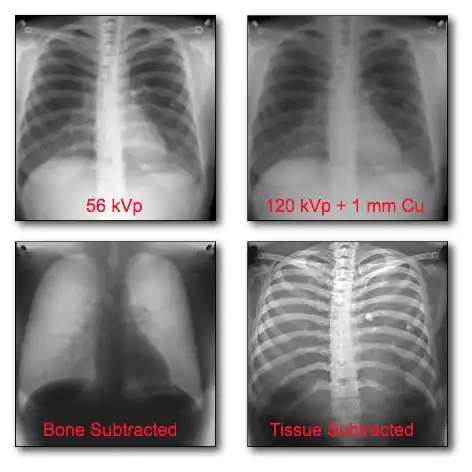

Dual-energy imaging can be used to eliminate bone information in an image, so that an image displaying tissues only is obtained. Alternatively, the technique can be used to generate the reverse effect where tissue information is eliminated and an image displaying bone only is generated. This latter option ideally allows the density of bones to be analysed. A theoretical background to this imaging technique will first be developed below with the discussion leading towards Dual-Energy X-Ray Absorptiometry (DEXA).

Dual-Energy Imaging

- CR and DR image receptors can generally be used for dual-energy radiography in either of two configurations: